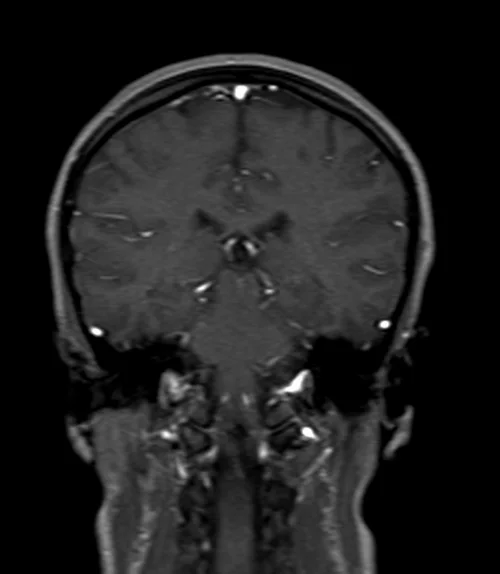

brain mri localizer image